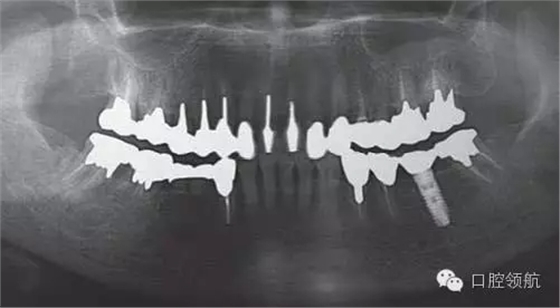

患者因?yàn)榉N植體出現(xiàn)松動來院就診。于外院接受的植入手術(shù)和修復(fù),最近感覺到開始出現(xiàn)松動。在附近口腔醫(yī)院就診,被告之因“種植體本身松動”需到大學(xué)附屬醫(yī)院就診,然后來我院接受治療。初診時的口腔內(nèi)所見, (右下第6顆牙) 修復(fù)體的松動以及周圍發(fā)紅的黏膜組織 (圖1)。(右下第6顆牙) 上部修復(fù)體咬合面金屬的露出,可能是為了防止上部修復(fù)體的旋轉(zhuǎn),修復(fù)體和鄰牙用樹脂進(jìn)行連接。從全景X線片上,可看到種植體和上部修復(fù)體之間有著細(xì)小的間隙(圖2)。

圖2 全景片顯示,種植體和上部修復(fù)體之間有著細(xì)小的間隙。

①全景或者X線牙片,通過影像觀察診斷上部修復(fù)體和種植體之間是否存在間隙,或種植體周圍是否能看到透射影像(圖2)。